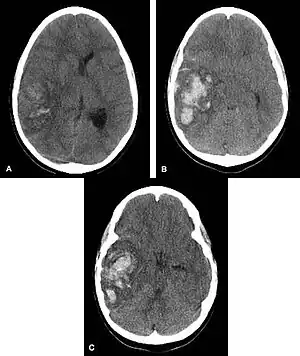

| Multiple intraparenchymal hemorrhage | |

Intraparenchymal hemorrhage (IPH) is one form of intracerebral bleeding in which there is bleeding within brain parenchyma. The other form is intraventricular hemorrhage (IVH).[1]

Intraparenchymal hemorrhage accounts for approximately 8-13% of all strokes and results from a wide spectrum of disorders. It is more likely to result in death or major disability than ischemic stroke or subarachnoid hemorrhage, and therefore constitutes an immediate medical emergency. Intracerebral hemorrhages and accompanying edema may disrupt or compress adjacent brain tissue, leading to neurological dysfunction. Substantial displacement of brain parenchyma may cause elevation of intracranial pressure (ICP) and potentially fatal herniation syndromes.